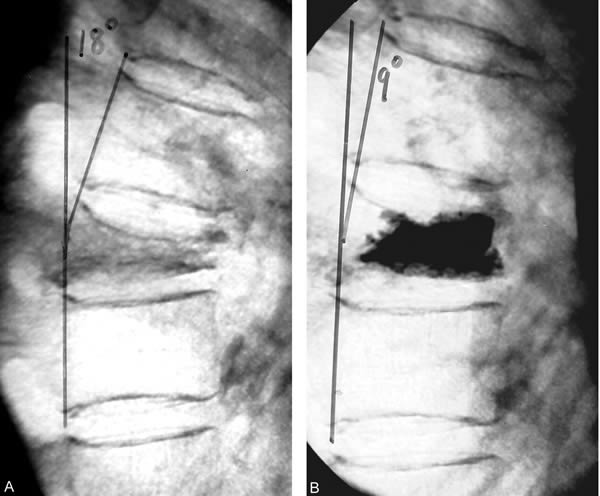

Here’s the money figure. The TRIALS line indicates quarter before publication of vertebroplasty trials in the NEJM. The AAOS line indicates quarter before release of the American Academy of Orthopaedic Surgeons statement on vertebral augmentation procedures:

Looking at the graph, it looks as though VAPS rates did decline after the studies. Indeed, as the authors reported:

The interesting observation really comes when the investigators break down declines in VAPS by specialty:

The striking differences by physician specialty were confirmed in the regression results. Interventional radiologists responded to the trials (column 7) with an increase in time trend of the vertebroplasty rate (+0.019, p = 0.046) and a percentage change after the trials that was not significantly different from 0. This was very different (p < 0.010) from physicians in other specialties, whose vertebroplasty rate declined by 73.1% after the trials (column 8). Interestingly, radiologists exhibited a greater decline in the kyphoplasty rate (−46.9%) than did other specialists (−21.7%, p < 0.010) (columns 9 and 10).

Remember, according to this database, interventional radiologists do far more vertebroplasties than they did kyphoplasties, while surgeons do more kyphoplasties than vertebroplasties. Also, kyphoplasty is viewed as a more “invasive” procedure than vertebroplasty, mainly because of the inflation of the balloon in the vertebral body. So it might be that radiologists were more willing to shy away from kyphoplasty, leaving that to surgeons, than they were vertebroplasty. Moreover, surgeons, viewing the “more invasive” kyphoplasty procedure as more “surgical” in nature, might be less willing to give it up, given that the two studies didn’t directly address kyphoplasty. However, it is disturbing that the rates of vertebroplasty done by interventional radiologists haven’t declines in Florida at all since these 2009 studies, while among other specialties have decreased their use of vertebroplasty markedly.